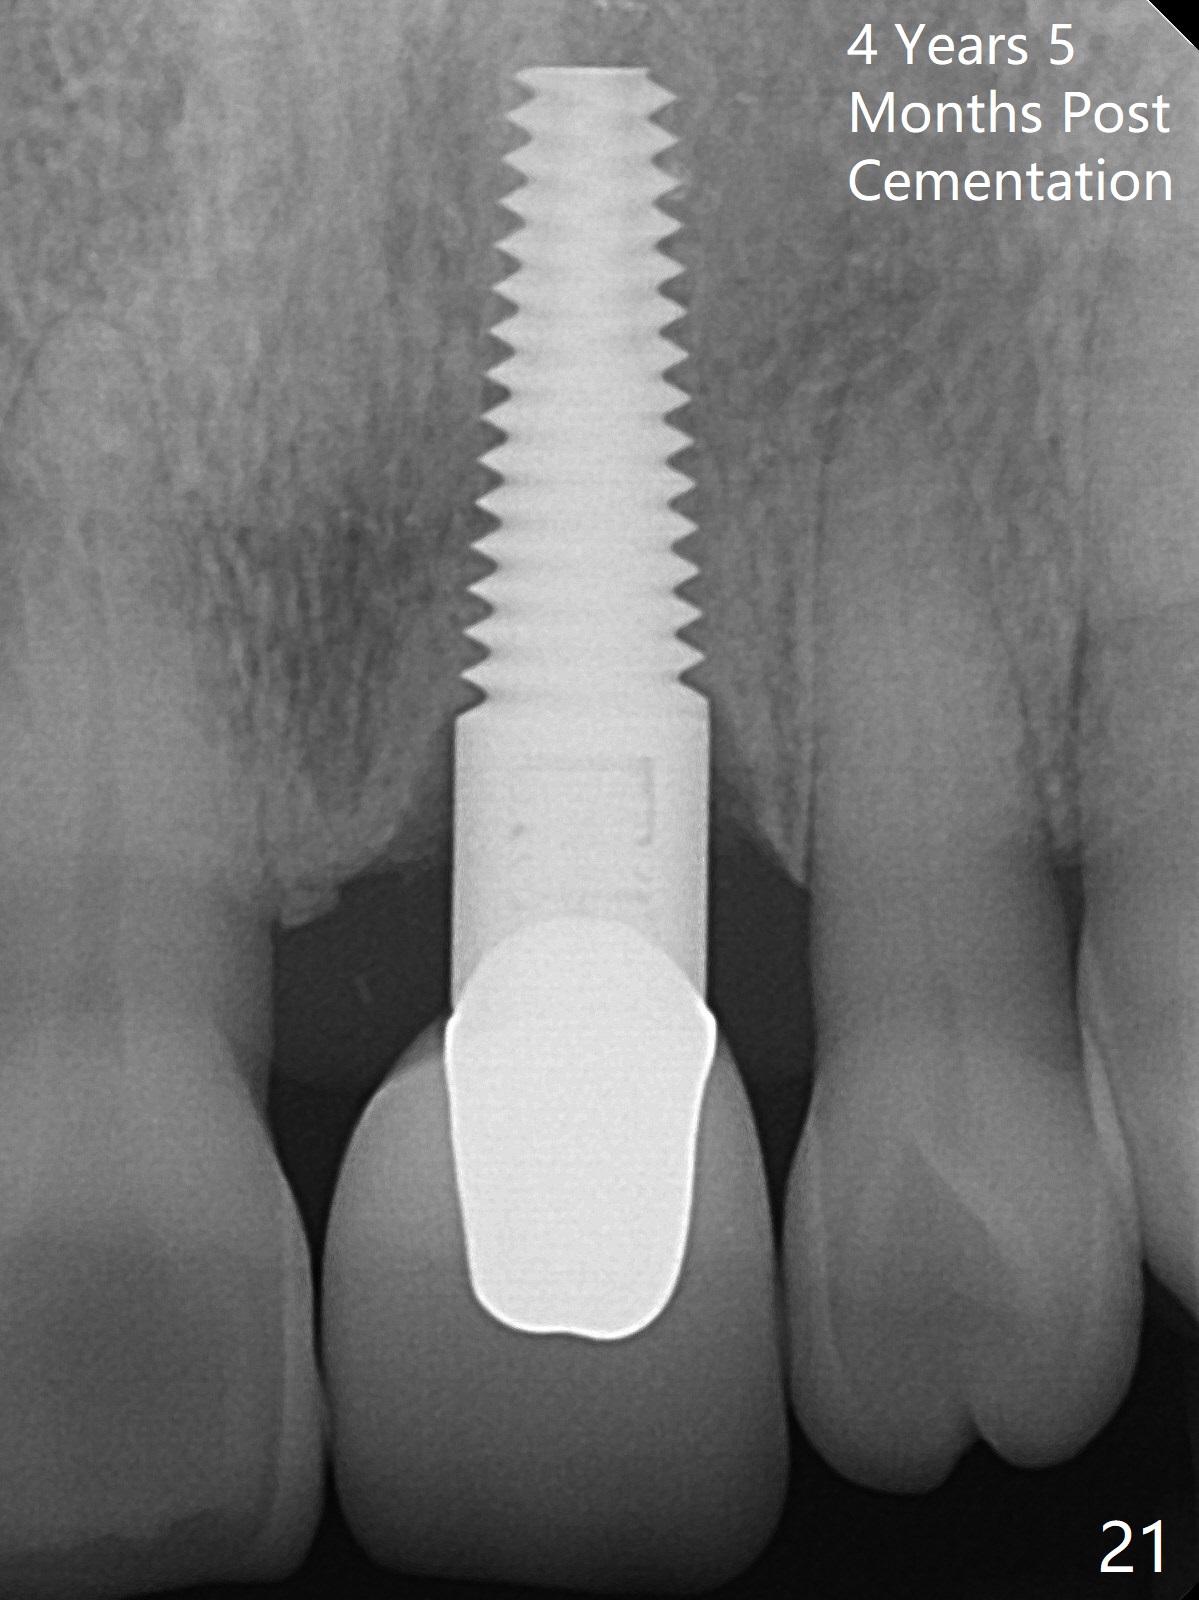

A 60-year-old lady had an abscess mesial to #9 six years ago (Fig.1,2 <), treated as a perio lesion by laser (Fig.3) and osseous surgery without bone graft (Fig.6, followed by CT exam revealing semi-circumferential bone loss (Fig.4,5). When the perio treatment failed, attention was paid to endo aspect (Fig.7-9). In fact the pulp was found to be vital when access to root canal therapy was made. As expected, the treatment failed again. The palatal fistula persisted. The infection was suspected to be a source of remote immediate implant site (#30). The tooth #9 was extracted. It appears that there is a semilunar crack line in the linguomesial root (Fig.12). When the socket healed 2 weeks post extraction (Fig.10), the #30 buccal defect was debrided with bone graft. There was no bone resorption 4 weeks post extraction (Fig.11); a 4.5x17 mm implant was placed (Fig.13-15). An immediate provisional was fabricated (Fig.16-18). Fig.19,20 were taken 3 months post implantation and 7 months post cementation, respectively. Dense bone forms around the implant coronally 4 years 5 months post cementation (Fig.21), while the gingiva is healthy palatally (Fig.22) and buccally (Fig.23).